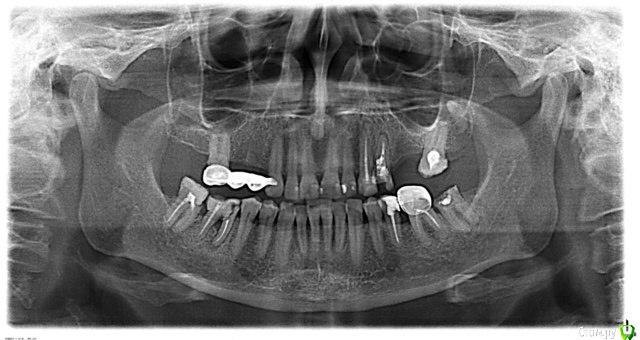

У меня немного странный запрос. Есть ли коллеги в г.Коломна, пациент - моя мама. К сожалению, сама нахожусь в декрете и не могу подготовить маму к протезированию. Ездить к моим коллегам в Москву на лечение тоже не очень хотелось бы. Может быть, кто-нтбудь возьмется за подготовку и дальнейшее протезирование, снимок прикрепила. Заранее спасибо.

post-32238-0-60328700-1609230910_thumb.jpeg